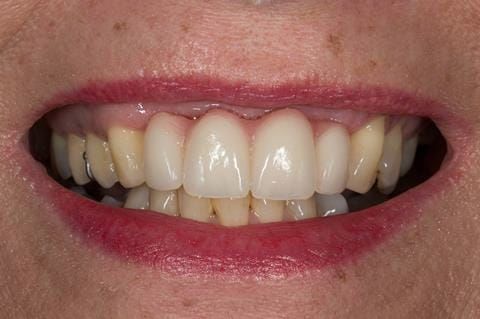

- High smile line showing gum above gingival zeniths of upper front teeth when smiling. Aesthetic failure of the upper four incisors with inflammation of the gingivae and mis-match of the gingival zenith levels.

- Extract the upper 2-2 teeth and replace with an interim acrylic based partial denture. Reline the interim denture over 9 - 12 months, replacing with a definitive cobalt chromium based partial denture. The definitive denture would ideally be designed as an occlusal protective splint to reduce the the potential for mechanical wear and breakages of the moderately/heavily restored maxillary dentition. In addition, should further upper teeth require extraction they could be added on to the denture cobalt chromium framework - therefore a new prosthesis would not be required as future teeth are lost. This option would produce an excellent aesthetic outcome. This is the option the patient chose to have.

Following consultation and second discussion appointment the patient chose to have option 3 namely, a maxillary cobalt chromium based partial denture/protective occlusal splint. The clinical situation and treatment process is shown in detail below with photographs. The patient was successfully rehabilitated with this and her quality of life considerably improved. The clinical work was provided by Finlay and the technical work by Rowan.